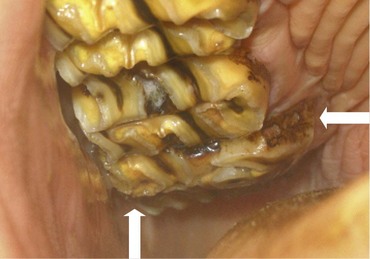

Fig. 8.11 A marked (circa 5 cm long) overgrowth is present on this caudally situated supernumerary mandibular CT (412) that has caused marked ulceration of the adjacent cheeks (arrow).

image

In other instances where a caudal supernumerary tooth develops at the same time as the normal 11, overcrowding of the dental buds occurs prior to calcification. In these cases, the 11 and the supernumerary cheek tooth are both deformed and lie obliquely or possibly parallel to each other in separate or a common alveolus. Following eruption of the supernumerary cheek tooth, diastemata between these two distorted teeth allow food impaction also leading to painful periodontal disease. Unopposed caudal supernumerary CT will overgrow if not reduced (Fig. 8.11) and the overgrown teeth will become displaced caudally, causing diastema formation (Fig. 8.9).

In the rare cases where clinically significant diastemata do not occur adjacent to a supernumerary cheek tooth, continuing eruption of the unopposed supernumerary tooth causes an overgrowth (usually at the caudal aspect of the CT rows) (Figs 8.9 & 8.11). Consequently, it is very worthwhile in horses with caudal CT overgrowths, especially with unexplained development of such overgrowths, not to just assume that they are overgrowth of an 11, but to carefully count the teeth to assess if a supernumerary tooth is present. If any doubt exists, latero-oblique radiograph can confirm the presence of supernumerary teeth, but care must be taken not to mistake two overlapping teeth for a single, wide tooth. Very rarely, a second supernumerary tooth (e.g., Triadan 113) will develop caudal to the initial supernumerary cheek tooth as illustrated by Dixon et al.16